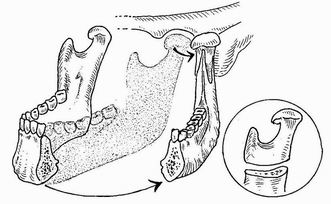

BPTM – Hemimandibulektomie

Masivní infiltrace měkkých tkání

Postižení spongiosy čelisti

Postižení mandibulárního kanálu

Primární kostní tumory čelisti

Exartikulace nebo resekce kloubního výběžku

Při šíření podél vertikálního ramene čelisti